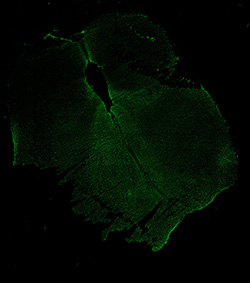

An anatomical analysis of the developing human midbrain from 6 post-conceptional weeks (PCW) to 22 PCW reveals increased tissue complexity, characterized by the emergence of dopaminergic nuclei, as highlighted by immunofluorescence analysis for tyrosine hydroxylase (TH).

MAP2

11PCW human midbrain

Merged